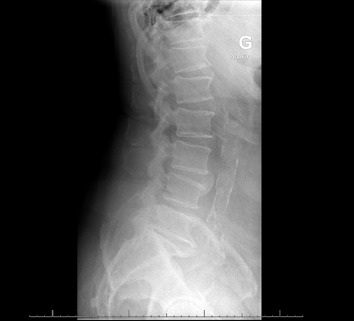

背景:尿气球菌是一种罕见的人类病原体,主要引起尿路感染、心内膜炎和菌血症。然而,它很少引起其他类型的感染,如脊柱炎。侵袭性尿支原体感染主要发生在有泌尿道疾病的老年男性中。实际发病率可能被低估了,因为气球菌生长在含二氧化碳的大气中,而尿液培养物通常不在这种环境中培养。有8例报告脊柱炎由尿单胞杆菌引起。材料和方法:我们报告了第9例发生在80岁的白人男性腰痛。患者有易感因素(糖尿病和泌尿外科手术史)。脊柱MRI显示脊椎椎间盘炎征象。两次针对椎间盘和腰肌的计算机断层引导活检没有诊断。10个血培养瓶中有一个培养出尿支原体。结果:在L2骨折恶化和不成功的经皮取样手术后,患者接受了T12至L4的手术稳定和多次活检。活检培养有尿气球菌。静脉滴注阿莫西林14天,口服左氧氟沙星3个月。结论:对于培养阴性的脊柱炎患者,尤其是有糖尿病和泌尿系统疾病的老年男性,应考虑尿支原体感染。

Background: Aerococcus urinae, a rare human pathogen, mainly causes urinary tract infection, endocarditis, and bacteremia. However, it is rarely the cause of other types of infection such as spondylodiscitis. Invasive A. urinae infection chiefly occurs in older men with underlying urinary tract disorders. The real incidence may be underestimated, as Aerococci grow in a CO2-containing atmosphere, and urine cultures are usually not incubated in this environment. There have been eight case reports of spondylodiscitis due to A. urinae. Material and Methods: We report a 9th case occurring in an 80-year-old Caucasian man with lower back pain. The patient had predisposing conditions (diabetes and a history of urological surgery). Spinal MRI showed signs of spondylodiscitis. Two computed tomography-guided biopsies targeting the intervertebral disc and psoas muscle were not diagnostic. One of 10 blood culture bottles grew A. urinae. Results: After worsening of an L2 fracture, and unsuccessful percutaneous sampling procedures, the patient underwent surgical stabilization of T12 to L4 with multiple biopsies. Biopsy cultures grew Aerococcus urinae. Amoxicillin was administered intravenously for 14 days, followed by oral levofloxacin for 3 months. Conclusion: A. urinae should be considered in spondylodiscitis with negative cultures, particularly in older men with diabetes and urological conditions.